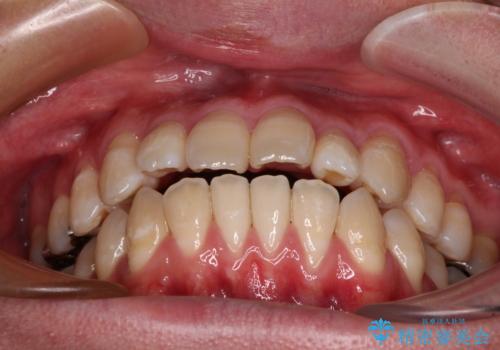

- 「横から見ると唇が前に出て見えるのが気になる…」

「マスクを外すのが恥ずかしい…」

そんな口元の突出感に悩まれてご来院された患者様。

精密検査の結果、上下左右の小臼歯4本を抜歯し、そのスペースに前歯を後方へ移動させる矯正治療をご提案しました。